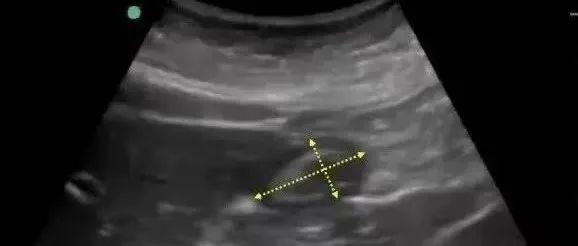

【跬步千里Tue】】重症超声可以进行肠功能的评价 part 2

肠道因其长度和曲折,是消化道检查最困难的部分,又因为肠道像心脏、肺等器官一样,是一个永远运动的器官,因此肠道功能的评估主要通过三个方面进行:宽度、厚度、活动度。宽度评估:小肠在未加压时,其宽度的测量往往指肠壁黏膜面至对侧肠壁黏膜面回声之间的距离。其中小肠(空、回肠)肠腔宽度一般小于2cm,大于3cm可判断肠管扩张;结肠内径一般小于5cm。厚度评估:肠壁厚度指肠壁浆膜面至黏膜面之间回声的距离。其中小肠厚度正常为2-3mm,大于3mm可诊断小肠肠壁增厚;结肠壁厚度约3-4mm,大于5mm可考虑肠壁增厚。需要注意的是,结肠肠壁上结肠袋及肠壁皱襞结构。...

【力学笃行】重症患者胃窦切面的评估

力学笃行胃窦切面的评估胃肠功能的评估对ICU患者来说十分重要,重症超声已经可实现在床旁对胃窦、胃底、空肠、回肠、右半结肠、左半结肠等形态及部分功能的评估,这节力学笃行为大家详细讲解一下如何利用超声评估胃窦。01胃窦标准切面的获取胃肠评估需在 6 个部位获取图像,包括胃窦、胃底、空肠、回肠、右半结肠、左半结肠。胃窦主要评价胃潴留及胃窦运动,图示红色箭头标记处就是超声获取胃窦切面的位置,在这里我们可以获取...